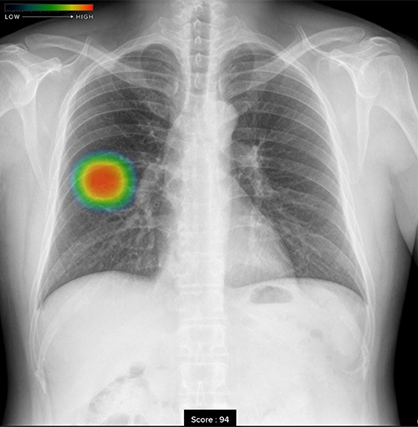

当院では、富士フイルム社のAI診断支援システム「CXR-AID」を導入し、胸部レントゲン画像をAIが自動解析することで、異常が疑われる部分を検出・表示しています。これにより、医師による確認を補助し、見落としの防止と診断精度の向上を図っています。

② ヒートマップ表示機能

撮影した胸部単純X線画像を自動解析し、結節・腫瘤影、浸潤影、気胸が疑われる領域を検出、確信度に基づいた表示を行います。確信度のスコアに応じて、画像はカラーコーディングによるヒートマップとして映し出されます。

画像単位の解析結果として、画像内の確信度の最大値が数値で表示されます。